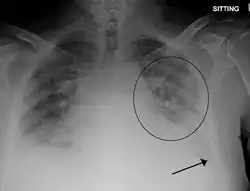

Chest X-ray has been used for many years to diagnose pulmonary edema due to its wide availability and relatively cheap cost.[4] A chest X-ray will show fluid in the alveolar walls, Kerley B lines, increased vascular shadowing in a classical batwing peri-hilum pattern, upper lobe diversion (biased blood flow to the superior parts instead of inferior parts of the lung), and possibly pleural effusions. In contrast, patchy alveolar infiltrates are more typically associated with noncardiogenic edema.[3]

Lung ultrasounds, employed by a healthcare provider at the point of care, is also a useful tool to diagnose pulmonary edema; not only is it accurate, but it may quantify the degree of lung water, track changes over time, and differentiate between cardiogenic and non-cardiogenic edema.[36] Lung ultrasound is recommended as the first-line method due to its wide availability, ability to be performed bedside, and wide diagnostic utility for other similar diseases.[4]